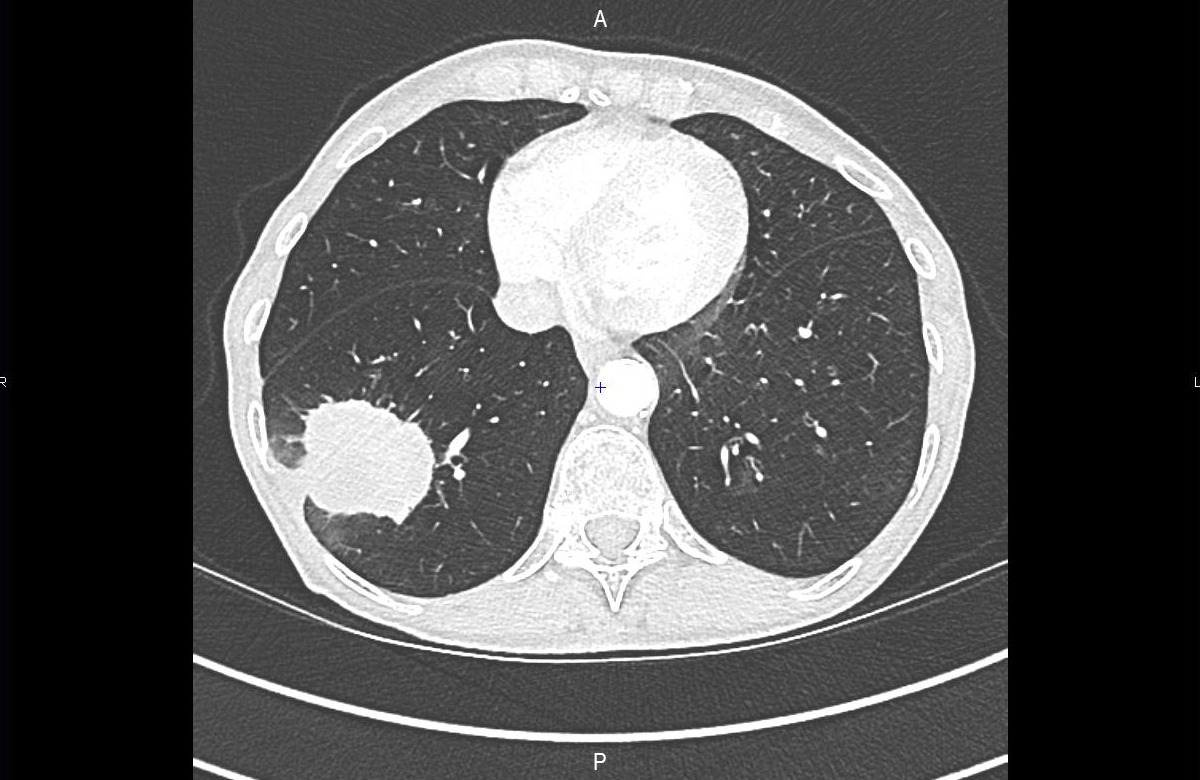

C’est une femme de 54 ans, qui a pour antécédents une appendicectomie, un surpoids, un diabète non insulino-dépendant bien contrôlé sous metformine et glimépiride. Elle n’est pas ménopausée, G3P2 (une fausse couche non explorée, deux grossesses menées à terme s’étant déroulées sans problème), elle porte un dispositif intra-utérin (DIU) au cuivre. Elle est fumeuse, et vous évaluez sa consommation tabagique à environ 17 paquets-années (1/2 paquet de cigarettes depuis l’âge de 20 ans).